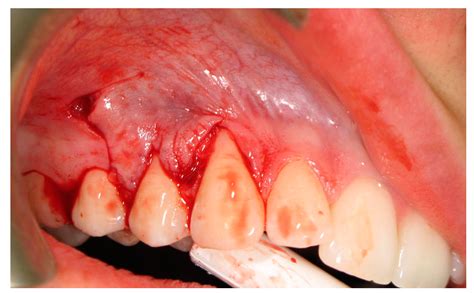

• Scaling and Root Planing: This deep cleaning procedure removes bacteria and tartar from below the gumline and smooths the root surfaces.

• Gum Grafting: In severe cases, a gum graft may be necessary to cover the exposed root and restore the gumline.

In severe cases, surgical intervention may be necessary to restore the gumline and cover the exposed root. Gum grafting is a common procedure used to treat gum recession. During the procedure, a small piece of gum tissue is taken from another part of the mouth and attached to the affected area. This helps to cover the exposed root and promote healing.

It is important to follow your dentist's recommendations for post-operative care to ensure a successful recovery. This may include avoiding hard or sticky foods, using a soft-bristled toothbrush, and taking any prescribed medications as directed.